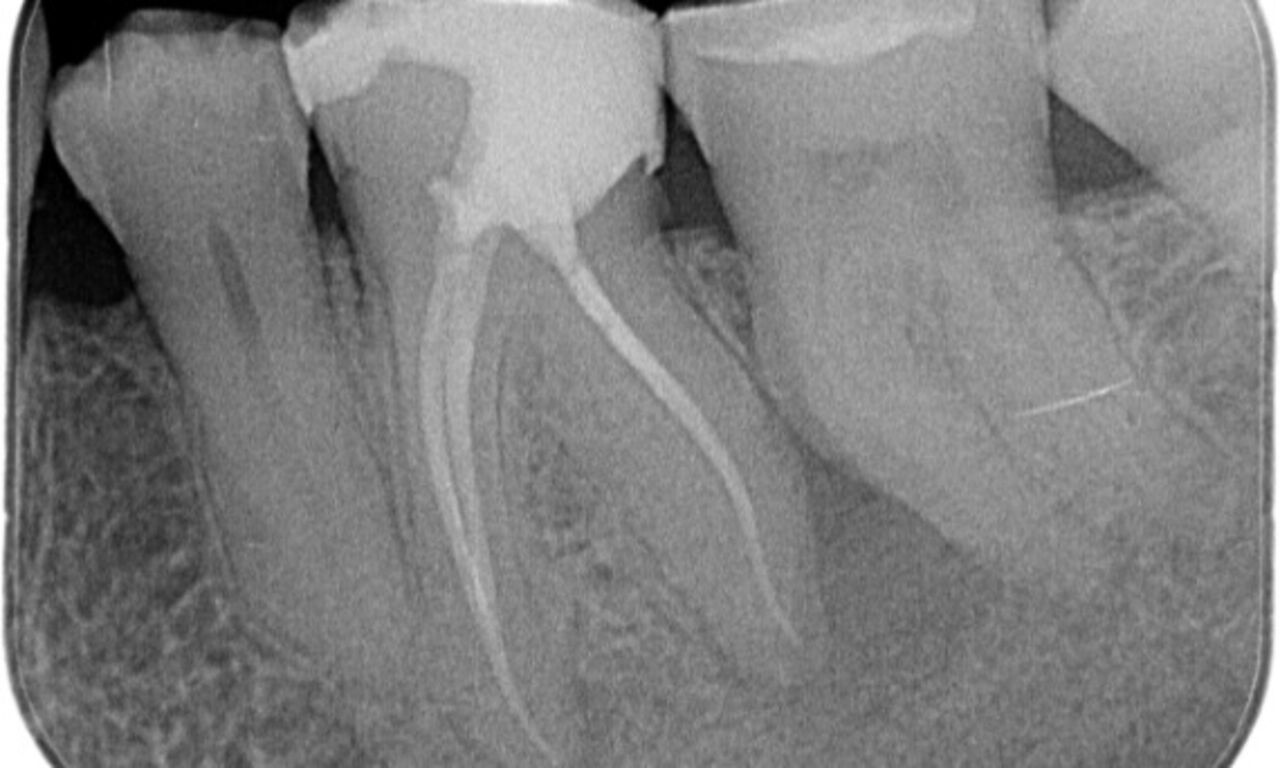

Upon examination, there was a caries lesion related to the lower right first molar. Radiographic examination revealed proximity of the lesion to the pulp horn and combining it with the chief complaint, a final diagnosis of chronic irreversible pulpitis was concluded.

Periapical radiolucency associated primarily with the distal root and loss of lamina dura on the mesial root.